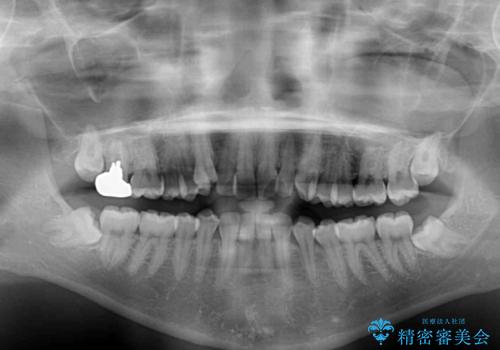

本人は気づいていませんでしたが、下顎前歯が2本欠損しており、上下の歯列がアンバランスとなりデコボコになっていました。

上下のバランスを取るため、上顎左右第一小臼歯2本を抜歯し、ワイヤー矯正を行うこととしました。